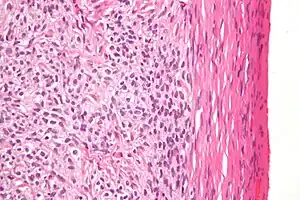

| Micrograph of a granulosa cell tumour, a type of sex-cord–gonadal stromal tumour. H&E stain. | |

By prevalence